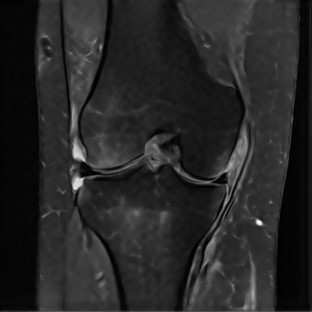

Limited by imaging systems, the reconstruction of Magnetic Resonance Imaging (MRI) images from partial measurement is essential to medical imaging research. Benefiting from the diverse and complementary information of multi-contrast MR images in different imaging modalities, multi-contrast Super-Resolution (SR) reconstruction is promising to yield SR images with higher quality. In the medical scenario, to fully visualize the lesion, radiologists are accustomed to zooming the MR images at arbitrary scales rather than using a fixed scale, as used by most MRI SR methods. In addition, existing multi-contrast MRI SR methods often require a fixed resolution for the reference image, which makes acquiring reference images difficult and imposes limitations on arbitrary scale SR tasks. To address these issues, we proposed an implicit neural representations based dual-arbitrary multi-contrast MRI super-resolution method, called Dual-ArbNet. First, we decouple the resolution of the target and reference images by a feature encoder, enabling the network to input target and reference images at arbitrary scales. Then, an implicit fusion decoder fuses the multi-contrast features and uses an Implicit Decoding Function~(IDF) to obtain the final MRI SR results. Furthermore, we introduce a curriculum learning strategy to train our network, which improves the generalization and performance of our Dual-ArbNet. Extensive experiments in two public MRI datasets demonstrate that our method outperforms state-of-the-art approaches under different scale factors and has great potential in clinical practice.